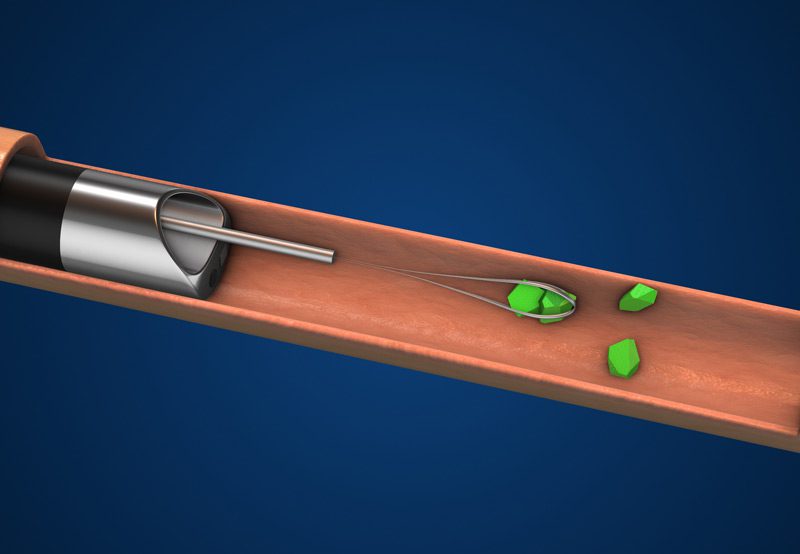

The procedure is typically done under general or spinal anesthesia. The ureteroscope is inserted through the natural urinary passageways, requiring no cuts or incisions. Once the stone is located, it is either removed with a small basket or fragmented using a laser, most commonly the holmium:YAG laser.